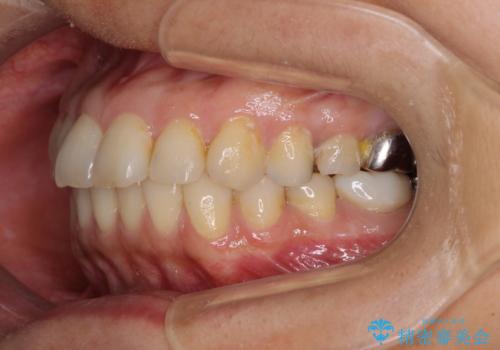

- 高校生の時に行った矯正治療の後戻りと、通院してもなかなか改善しない奥歯の痛みを気にして来院された患者様です。

左下奥歯は、前医より難治性なので抜歯も考えるよう言われたそうですが、一度もラバーダムを用いた根管治療はされていないとのことでした。

まずは左下奥歯の根管治療を行い、痛みが引いたことを確認してから矯正治療を開始しました。

矯正治療後には、左下奥歯の症状がないことを確認し、セラミッククラウンにて補綴治療を行うこととしました。